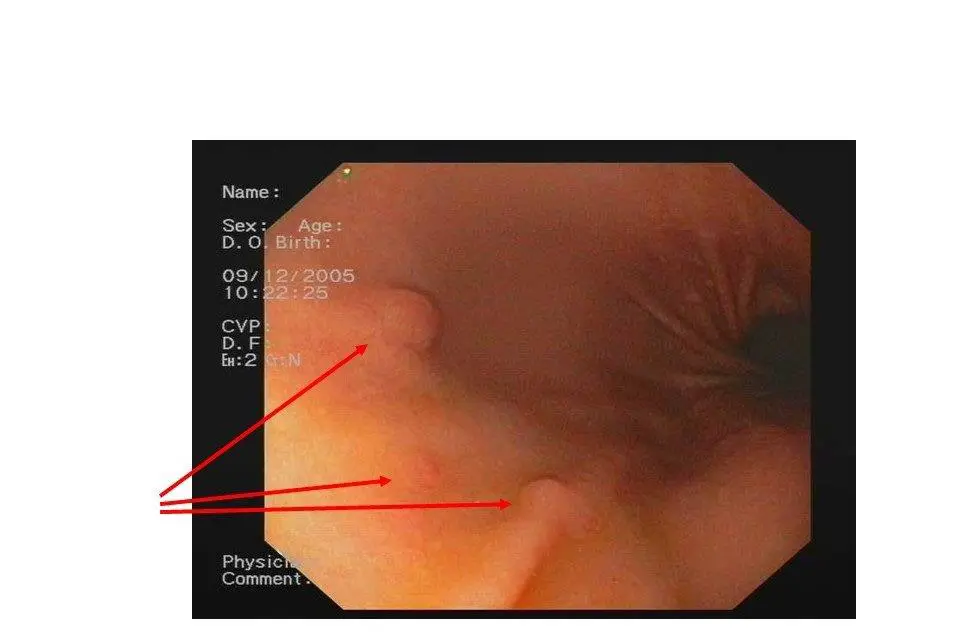

Gastroskopi

Utføres ved at en slange med et videokamera i enden føres via munnen nedover i spiserør, magesekk, tolvfingertarm og litt videre nedover i tynntarm. Undersøkelsen gir god oversikt over innsiden av disse organene. Man kan ved denne prosedyren ta vevsprøver av sykelige tilstander som måtte påvises.

Bildet viser flere nevroendokrine svulster, og er tatt gjennom gastroskop. Den største svulsten måler 5 mm. Foto: Gastroenterologisk undersøkelsesavdeling, Oslo universitetssykehus